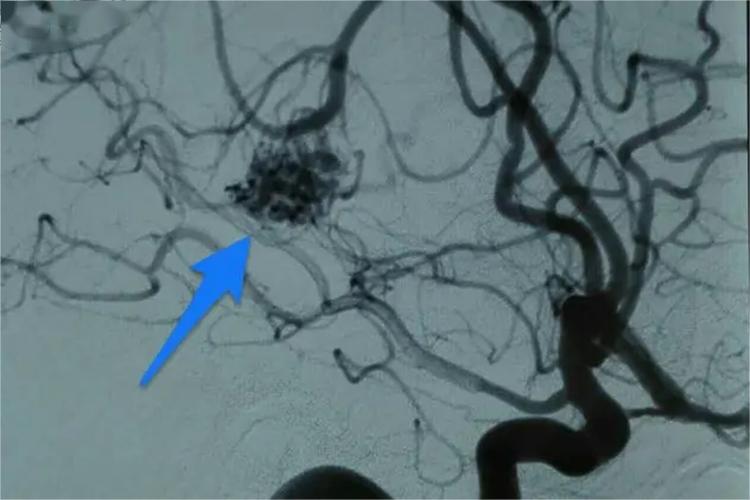

血管畸形主要有微静脉畸形、静脉畸形和动静脉畸形。微静脉畸形多见于颜面部皮肤,表现为不规则形状大小不一的鲜红或紫红色,可为小斑点或数厘米,与皮肤表面平齐,界限清楚。用手按压,表面颜色褪去,解除压力后病损恢复;静脉畸形表浅者呈蓝色或紫色,病损位置深者表面皮肤及黏膜正常。柔软,扪之可被压缩,有时可扪及静脉石,边界不清,可引起疼痛和肿胀;动静脉畸形好发于颞浅动脉所在的颞部和头皮下组织,呈念珠状,有搏动感,表面温度比正常高,扪之可有震动感,听诊可有吹风样杂音。